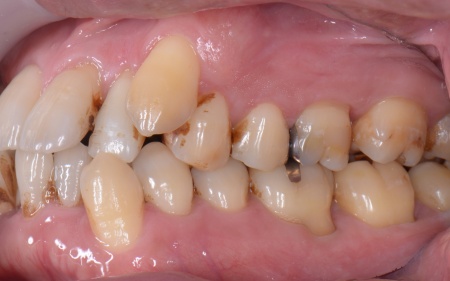

拝見したところ、上下の歯は、ずれたりねじれたりしてデコボコに生えており、著しく歯並びが乱れていました。

またレントゲン撮影をして確認すると、右上前歯は顎の骨の中に埋まっている骨性埋伏(こっせいまいふく)の状態でした。

本来、骨性埋伏の歯は、歯茎を切開して中の歯を引っ張る開窓牽引(かいそうけんいん)を行うのが一般的ですが、患者様の歯は骨の中に深く埋まっていたため、開窓牽引は難しいと考えられます。

さらに、左下奥歯は重度の歯周病であり、歯を支えている骨が一部溶けていることが判明しました。

このまま放置すると骨がさらに溶け、歯を残すことが難しくなるおそれがあります。

骨に埋まっている右上前歯は引っ張り出すことができないため、隣の歯である右上奥歯(第1小臼歯)を代用歯として機能させる方法を選択しました。